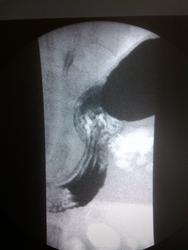

Пациентка, 68 лет. Направительный диагноз: ГПОД?

На 6-м снимке возможно скользящая грыжа.

Я б поставила.

Они направляют. А мы - исключаем. Снимки в полезных проекциях, правда, пока не снимаем.) Поэтому на стопудово Никто:) без Вашей подписи и не скажет.)